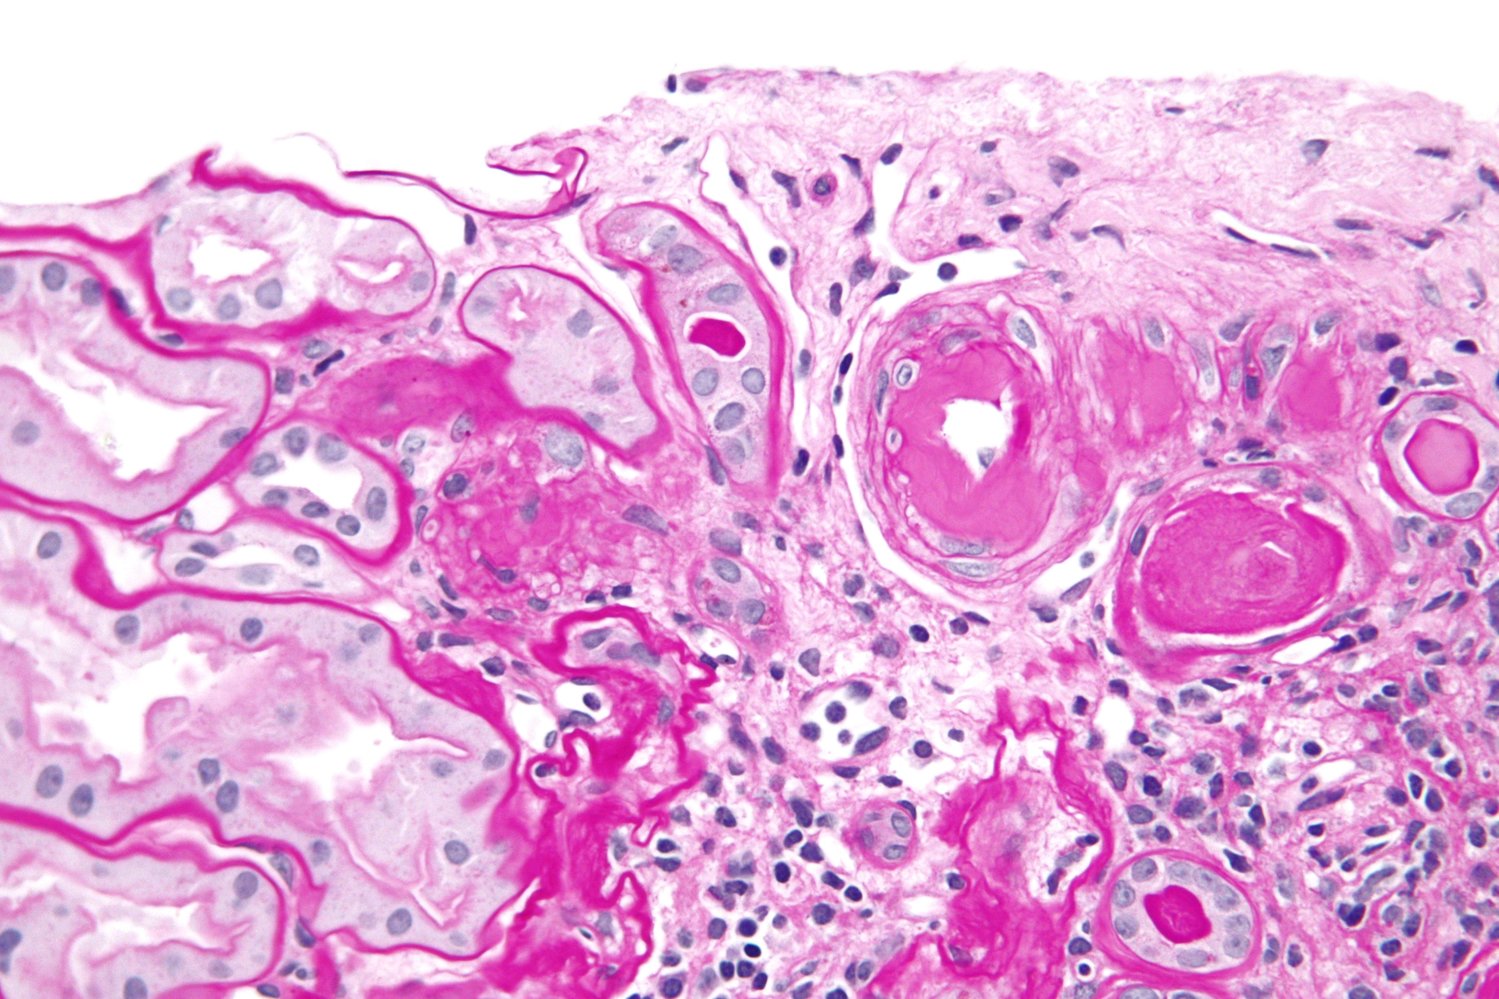

Hyaline arteriolosclerosis

- Deposition of proteins below the endothelium due to plasma protein leakage

- H&E: pink amorphous deposits (hyaline) within the arteriolar walls

- Causes: chronic essential hypertension, diabetes mellitus, and normal aging

Hyperplastic arteriolosclerosis

- Proliferation of subendothelial smooth muscle cells in response to very high blood pressure

- H&E: "onion-skin" appearance of the arteriole

- Cause: malignant hypertension